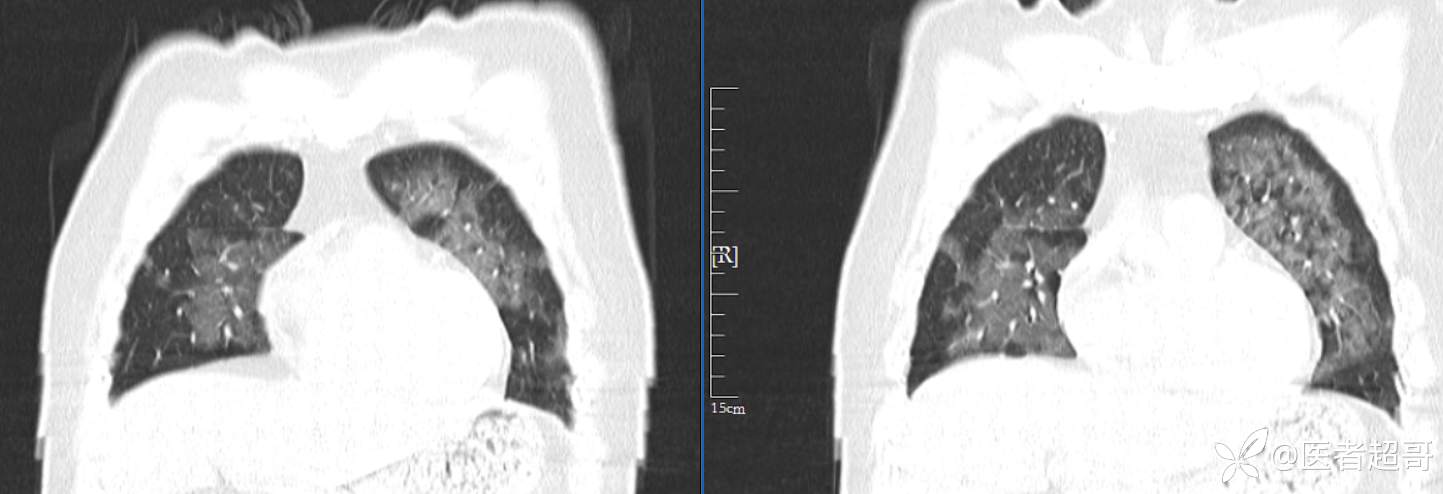

患者性别:女

患者年龄:47岁

主诉:胸痛就诊

简要病史:因“胸痛就诊”,行冠脉CTA检查,数小时后出现高热,伴畏寒寒战、气喘,暗红色泡沫样痰。

急性肺水肿 (17)